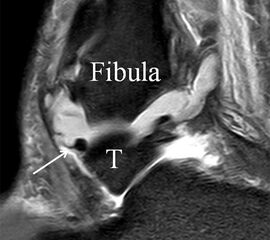

Der Ursprung des Ligamentum fibulocalcaneare liegt unmittelbar kaudal und dorsal des Ursprungs des Ligamentum fibulotalare anterius, so dass gehäuft kombinierte Verletzungen und auch ein gemeinsamer knöcherner Ausriss beobachtet werden. Nach kaudal dorsal verläuft das Band dann nach medial konvex unter die Peroneussehnen. Danach ist ein schräg deszendierender, gestreckter Verlauf bis zum calcanearen Ansatz abgrenzbar (Abb. 10). Dieser zu allen drei Standardebenen schräge Verlauf erschwert häufig die Diagnostik des LFC vor allem bei subtileren Verletzungen. Spezialprojektionen, die dem Bandverlauf orthograd folgen (entweder schräg coronar oder schräg sagittal) erleichtern auch hier die Diagnostik (Abb. 11) insbesondere nicht dislozierter Avulsionen. Assoziierte Verletzungen der Peroneussehnenloge müssen mit beurteilt werden, wobei neben Verletzungen der Sehnen und Sehnenscheiden die Beurteilung des Retinaculum peroneum superius und inferius wichtig ist. In einem Kollektiv von Patienten mit chronischen Außenbandinstabilitäten weisen 50% der Patienten eine Verletzung dieser Strukturen auf 5. Auch hier erleichtern hochauflösende Techniken die Diagnostik (Abb. 12).